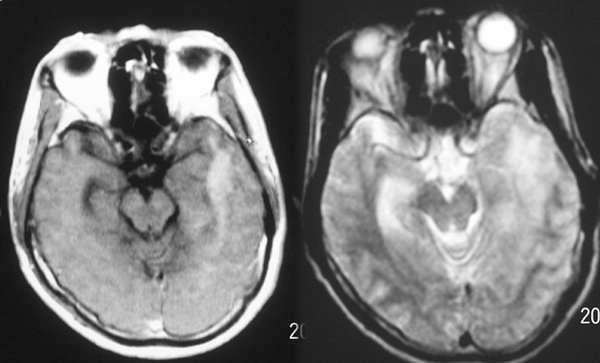

mr是增强

左侧基底节额颞叶稍长t1长t2信号,增强见边缘与脑回样强化,作侧脑室变窄。ct平扫呈等与扫地密度以等密度为主。考虑1脑炎。2脑肿瘤[淋巴瘤]

ct示左颞叶等,略低密度影,mr示左额颞叶t1wi呈低信号,t2wi呈高信号,增强后边缘不均匀强化,左侧脑体部明显受压,考虑脑梗塞可能性大

首先考虑脑梗塞,肿瘤mri表现多为长t2信号,增强后多有明显的不均匀强化,本病例占位征象明显,如果是肿瘤恶性度是偏高的,增强后应该有明显的强化表现。临床病史比较短暂,增强后强化呈条片状,梗塞在三天为水肿高峰,占位明显。综合考虑脑梗塞可能性大。

炎症可能性大,疱疹病毒性脑炎?